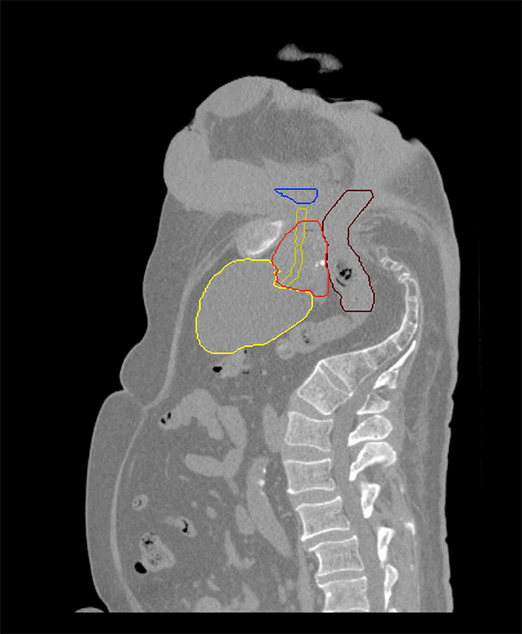

Planning CT Images